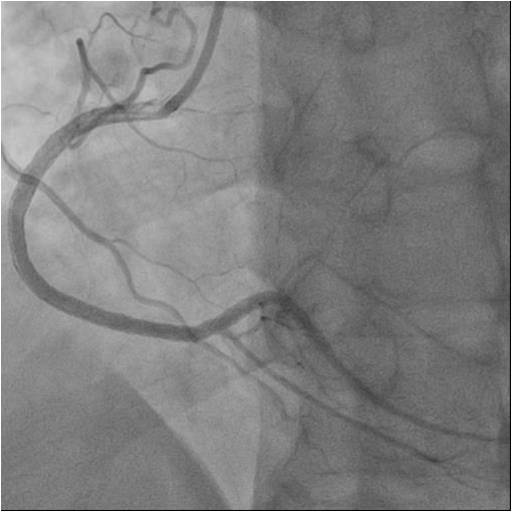

Complex PCI - CTO

Retrograde Recanalization of Chronic Occlusion of the Right Coronary Artery

Numerousattempts of antegraderecanalization using guidewires of different stiffnesswere unsuccessful. Pts ofretrograde recanalization using guidewires of different stiffnesswereunsuccessful. Another attempt at antegraderecanalization led to dissection dista RCA. Retrograde recanalization was performed using the technique of «kissing-wire». retrograde guidewire was inserted into theproximal segment of the RCA. Guidewire was externalized into the guide catheterusing Reverse CART technique. The tip-in technique was used for the Corsairantegrade microcatheter over the retrograde wire. Tthe microcatheterwassuccessfully inserted into the distal segment of the RCA. A soft antegradeguidewire was placed. A balloon catheter 2.0x30 mm was used for predilation inthe proximal middle and distal segments of the RCA at 14 atm. Consecutive DES2.75x44mm, DES 2.75x44mm, DES 3.5x39 mm stents were implanted in the distal,middle and proximal segments of the RCA, at pressures up to 16 atm.

Contralateral imaging is mandatory in the absence of intrasystemic collaterals. The availability of instruments and the ability of the team to use retrograde recanalization techniques, is an important prerequisite, for the interventional laboratory. Bilateral transradial access 6 Fr, in most cases allows to carry out retrograde recanalization of CA comfortably.